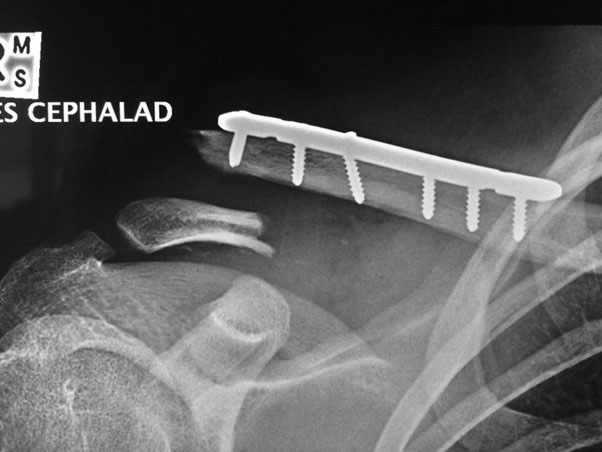

This time he didn’t wait around for treatment overseas, and flew straight back home. He effectively went from the airport to my rooms to the operating theatre that afternoon. This time around I needed to remove the original plate which had held the mid-shaft clavicle aligned while it healed, and replace it with a longer plate which would grab the new fracture fragments at the end of the clavicle (see image below).

Fracture of distal clavicle next to existing plate after fall from mountain bike